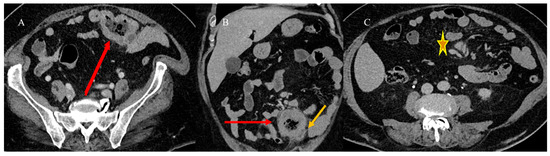

2.4. Small Bowel Tumors Causing Small Bowel Occlusion

- Kroepfl, V.; Bellotti, R.; Gasser, E.; Esswein, K.; Esser, H.; Kafka-Ritsch, R.; Öfner, D.; Perathoner, A. Small bowel neuroendocrine tumors: An analysis of clinical presentation, diagnostic workup and surgical approach—A single center retrospective study. Front. Surg. 2023, 10, 1072435. [Google Scholar] [CrossRef]

- Basendowah, M.H.; Ashour, M.A.; Hassan, A.Y.; Alshaynawi, S.; Alyazidi, L.K. Multiple small intestinal neuroendocrine tumors with findings of intestinal obstruction. Cureus 2021, 13, e17629. [Google Scholar] [CrossRef] [PubMed]

- Behi, H.; Omry, A.; Dallagi, R.; Changuel, A.; Troudi, D.; Khalifa, M.B. Diagnosing and managing small bowel neuroendocrine tumors presenting as acute obstruction in an elderly patient: A case report and comprehensive management overview. Int. J. Surg. Case Rep. 2024, 122, 110126. [Google Scholar] [CrossRef]